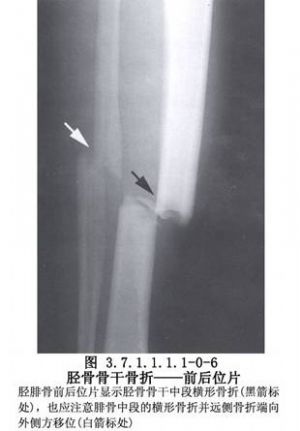

脛骨幹骨折不癒合有多種手術治療方法,需要根據骨折不癒合的類型、骨折對位對線及軟組織情況予以選擇。但要注意儘量選用方法較簡單,創傷小和局部血循環破壞少的手術。脛骨幹骨折影像表現及解剖見下圖(圖3.7.1.1.1.1-0-5~3.7.1.1.1.1-0-8)。